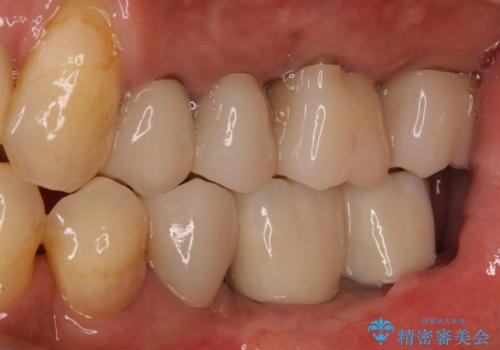

インプラント埋入後、手前のインプラント周りの丈夫な歯肉(角化歯肉)が失われてしまったため、角化歯肉の移植を行うこととなりました。

十分な角化歯肉が獲得でき、清掃性の高い環境が達成されました。